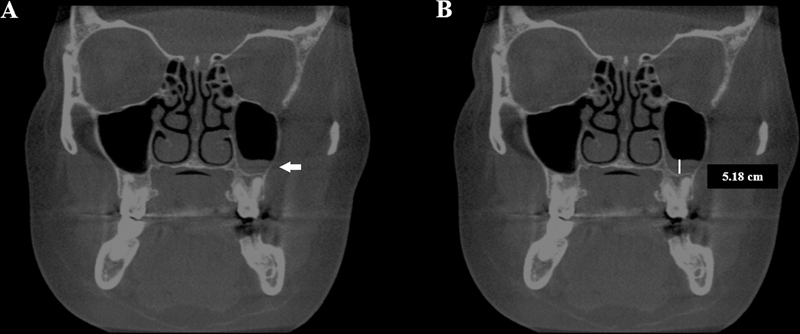

Methods: There were 297 CBCT exams assessed by two examiners who evaluated the presence of CB (> 50% pneumatization of the turbinate's height), NSD (deviation point of the nasal septum and crista galli angle >9 o ), and mucosal thickening of maxillary sinuses (mucosa around the sinus walls > 3 mm in height). The association between CB and side, NSD, mucosal thickening of the maxillary sinuses, sex, and age were evaluated by the chi-squared and Fisher's exact tests (α = 5%).

Results: A total of 208 CB was found, corresponding to 11.7% of the evaluated turbinates, being more prevalent in the middle one ( p  < 0.0001). Considering all exams, 132 (44.4%) had at least one CB. There was an association between the presence of middle left CB with NSD ( p  = 0.028). No other significant associations were found ( p  > 0.05).